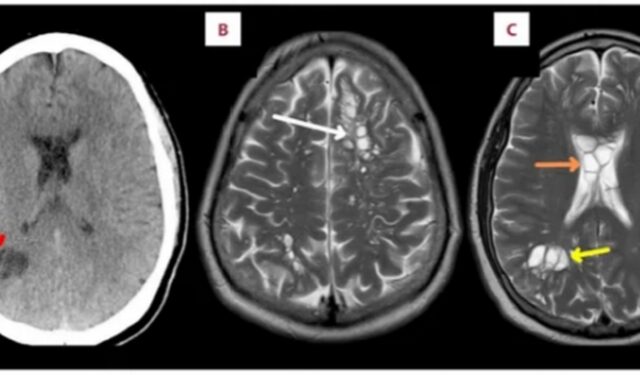

Όπως αναφέρει η δημοσίευση που έγινε στο American Journal of Case Reports, σε αξονική τομογραφία αποκαλύφθηκε πως είχε αξιοσημείωτο σύμπλεγμα κύστεων στην κάτω δεξιά γωνία του εγκεφάλου του. Του έκαναν αμέσως εισαγωγή, με τη μαγνητική τομογραφία να αποκαλύπτει και άλλες κύστες σε άλλα σημεία του εγκεφάλου, καθώς και οίδημα.

Η κατανάλωση αυγών ή προνυμφών T. solium οδηγεί συχνότερα σε μια κατάσταση που ονομάζεται ταενίαση (μικροί κλειστοί σάκοι ή κύστες των προνυμφών του σκουληκιού συσσωρεύονται στα έντερα ενός ατόμου). Ο εν λόγω, ανέπτυξε κυστικέρκωση, εκδοχή της λοίμωξης κατά την οποία οι κύστες ενσωματώνονται σε διαφορετικό ιστό -όπως ο μυς ή ο εγκέφαλος.

Όταν ενσωματώνονται στο νευρικό σύστημα, η κατάσταση ονομάζεται νευροκυστικέρκωση. Προκαλεί συχνότερα πονοκεφάλους και επιληπτικές κρίσεις, με το τελευταίο σύμπτωμα να βιώνει έως και το 80% των ασθενών. Η σοβαρότητα των συμπτωμάτων συνήθως εξαρτάται από τις δομές και τους ιστούς του εγκεφάλου που έχουν μολυνθεί από τα σκουλήκια.